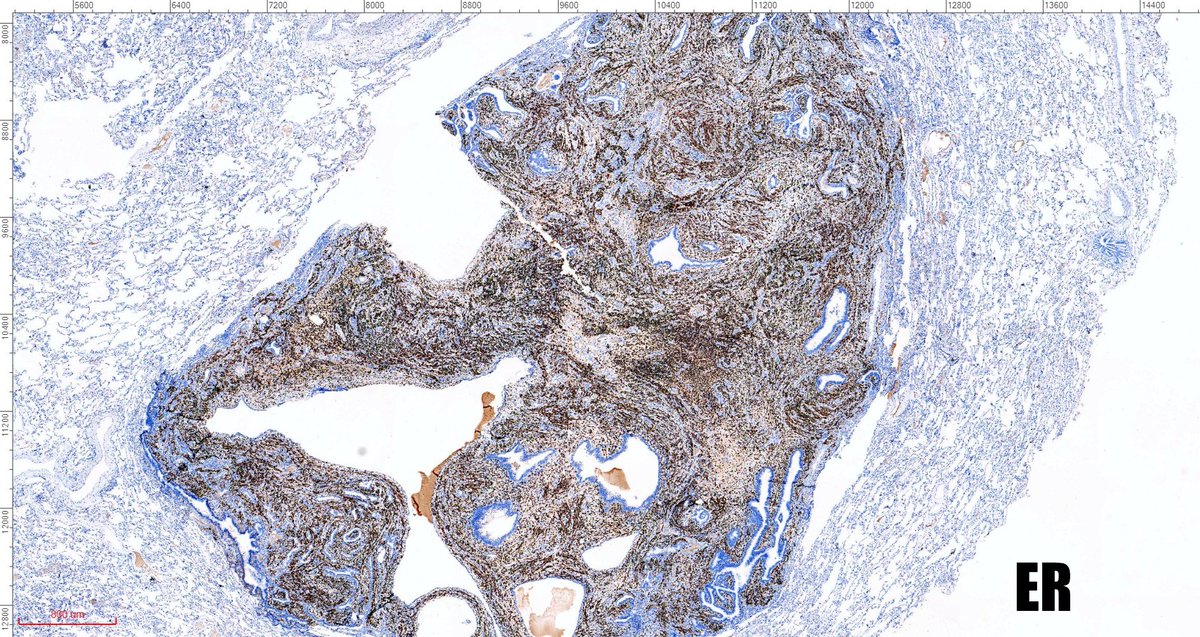

One of the most cryptic lesions for me in #pulmonarypath is the so called benign metastasizing leiomyoma. This case is a 37yo after myomectomy 3 years ago.

fabiotavora's tweet image. One of the most cryptic lesions for me in #pulmonarypath is the so called benign metastasizing leiomyoma. This case is a 37yo after myomectomy 3 years ago.